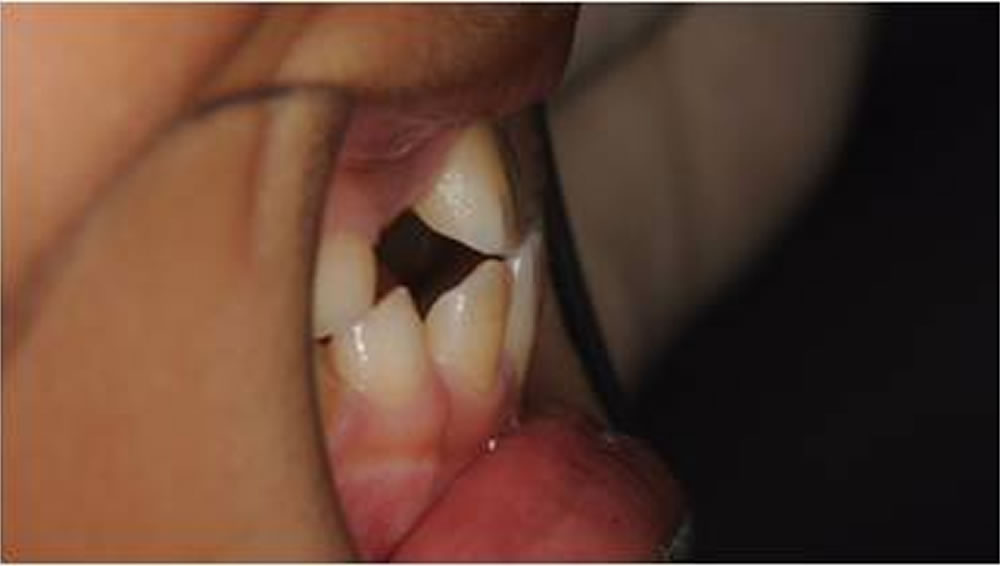

BiVi歯科・矯正歯科で実施した小児矯正の治療例をご紹介

▼当院で実際に行った小児矯正治療の症例をご紹介します。